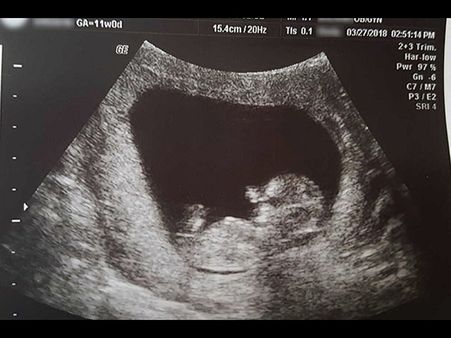

Brave Mum Shares Pictures Of Her 14-Week-Old Foetus

There is no greater loss than losing a child. A woman shared her sad story of losing her 14-week-old foetus and shared a post on what she felt about the whole thing!

The brave mum also shared heartbreaking pictures of her 14-week-old foetus! The images will just break your heart!

She posted the images of the 14-week-old foetus that she had to abort. The whole idea about sharing the picture was to show that the foetus was 'fully formed' even though it was just four inches long and it weighed 0.05 pounds!